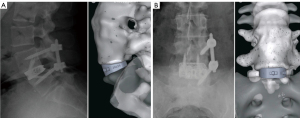

OTS ALIF implants have also benefited from advancements in 3D printing technology. While PS implants are tailored to individual anatomical contours, OTS implants now incorporate micro modifications, such as increased porosity and altered surface textures, specifically designed to enhance arthrodesis and improve implant longevity. Although OTS implants maintain a standardized structure to accommodate a broader population, they share the same advanced material composition and surface technologies as PS implants. The primary difference lies in customization; OTS implants offer a uniform design, while PS implants are uniquely crafted to meet the specific anatomical needs of individual patients (Figure 5A,5B). Both types of implants leverage 3D printing advancements to optimize clinical outcomes and enhance patient care.

PS implants are meticulously engineered to conform to the individualized anatomical contours of each patient, addressing the complex geometric irregularities often present in pathological anatomy. This custom-tailored approach allows surgeons to design implants with precise dimensions and asymmetric sides as needed (12,16,18) (Figure 3). Custom design features include corrective angulation to restore lumbar lordosis, screw holes with preplanned trajectories that account for specific screw lengths, and end plate interface geometry matched to the patient’s unique anatomy (Figure 4). These enhancements ensure uniform loading across the end plates and implant, facilitating optimal integration with surrounding bone structures and significantly increasing the likelihood of achieving the desired preoperative alignment and biomechanical goals (23).

At the macroscopic level, the implant shape can be customized to perfectly match a patient’s unique anatomy, ensuring optimal fit and function within the intervertebral space. These “patient-specific” (PS) implants are tailored to the individual using anatomical data from imaging studies like computed tomography or magnetic resonance imaging scans (12) (Figure 2).